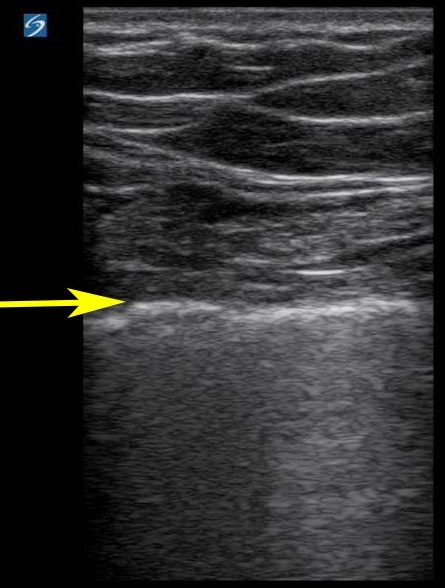

肺滑行 M 模式编号图像